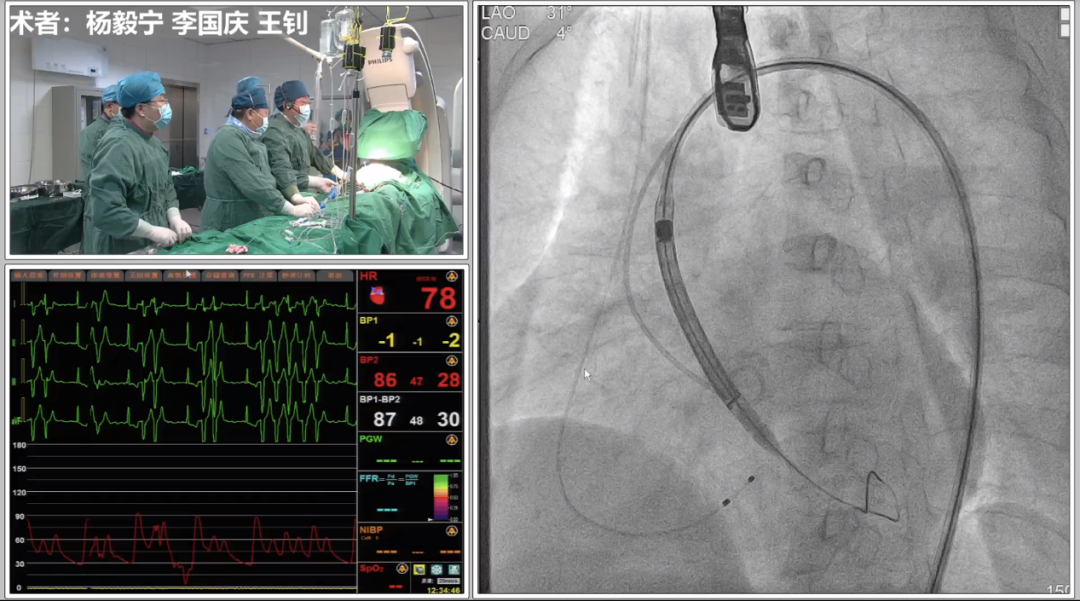

首先进行球囊预扩、造影,判断左右冠开口情况,实际显示冠脉灌注良好,将根据瓣膜植入后情况再决定是否进行冠脉干预,由于患者血管入路短径小于5.5mm,使用大鞘将难以通过并造成血管损伤,采用内联鞘直接进入递送系统,超强的顺应性使得递送顺利过弓和跨瓣。

在CUSP OVERLAP投照角度下进行瓣膜释放,释放过程中杨毅宁教授密切关注患者各项体征指标以及各器材位置情况,稳步操作最终达到预计位置精准定位,术后跨瓣压差即刻降低至0,患者双侧冠脉灌注良好,无反流,超声检测血流动力学明显改善,手术取得圆满成功。 中心简介 新疆维吾尔自治区人民医院始建于1934年,是一所集医疗、教学、科研、预防、保健和社区卫生服务为一体的大型综合性“三级甲等医院”。曾先后荣获“全国文明单位”、“全国百佳医院”、“全国五·一劳动奖状”、“全国卫生系统先进集体”、“全国万名医师支援农村卫生工程先进集体”、“全国十大百姓放心医院”、“全国卫生系统思想政治工作先进集体”、“自治区民族团结进步模范单位”等荣誉称号,是中国医院竞争力·顶级医院100强。 专家简介 杨毅宁 新疆维吾尔自治区人民医院 医学博士,博士生导师,教授、主任医师。 现任新疆维吾尔自治区人民医院党委副书记、院长。2004年和2007年分别于新加坡国立大学医院导管室和德国Mainz Johannes Gutenberg大学临床医院心内科研修冠状动脉介入治疗。目前研究方向为冠心病、先天性心脏病及瓣膜病的介入治疗及相关基础研究。国务院特殊津贴专家,新疆自然科学专家。2017年入选“国家百千万人才工程”并被授予“有突出贡献中青年专家”荣誉称号,第十二届“中国医师奖”获得者,先后入选教育部新世纪优秀人才计划,自治区“天山雪松计划”科技创新领军人才后备,“天山英才”培养计划第一层次。 主持国家重点研发计划1项,国家自然科学基金6项,教育部新世纪优秀人才计划项目1项,自治区级科研项目14项,参与国家自然科学基金、国家“十一五”计划子课题及横向课题、自治区重大专项等20余项研究。以第一作者或通讯作者身份发表学术论文250余篇,其中SCI收录论文60篇,CSCD收录论文174篇。主参编专著16部,荣获自治区科技进步奖10项,其中一等奖4项、二等奖6项,荣获中华医学科技奖2项,2020年被评为自治区“最美科技工作者”。在临床工作中不断开拓创新,年均完成经皮冠状动脉介入治疗(PCI)2000余例,先心病介入封堵术350余例,积极开展和推广IVUS、OCT、远隔缺血适应治疗等新技术的临床应用。在疑难危重症治疗上,使用TAVR、ECMO等新技术,成功救治多名危重冠脉、先心病、瓣膜病患者。